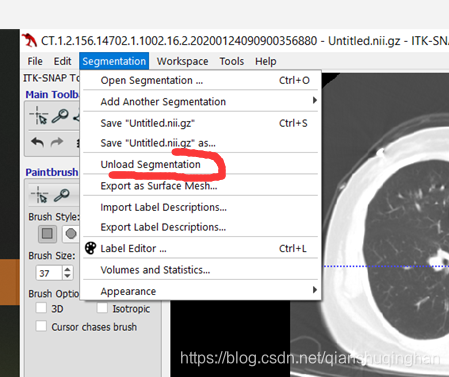

载入此前标注的mask文件

从菜单栏Segmentation->Upload Segmentation 选择mask文件载入;

或者直接拖拽进软件窗口。

然后选择Load As Segmentation即可。